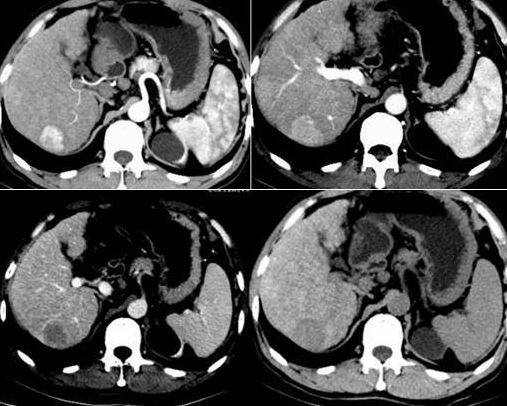

“是不是误诊了啊医生 , 我才24岁 , 就肩膀酸痛 , 怎么会确诊肝癌呢?”内科办公室 , 一个非常精致又不艳丽的女孩 , 皱着眉不停地追问医生 。

小七(化名)今年是本命年24岁 , 在老家蚌埠一家超市做收银员 , 前段时间总是觉得乏力、精神不好 , 那时候也并没有太在意 , 就觉得是没休息好的原因 , 请了病假回去休息一周 。

过了好几周 , 小七经常觉得很烦躁 , 而且脸上还大量地长痘 , 肩膀也变得酸痛 , 不得已才到医院做了检查 , 于是就有了开头的一幕 。

小七是一个非常喜欢干净的女孩 , 而且为了身体健康 , 她每天都要吃一个水煮蛋 , 而这个年轻女孩肝癌的根源 , 就是这个不起眼的水煮蛋 。

案例中小七就是因为肩膀酸痛就医检查 , 结果被查出了肝癌 , 我们的肩膀跟肝脏有什么联系呢?为什么会因为肩痛就查出肝癌 。

肝脏本身不具备痛感神经 , 不过肝脏很“聪明”地影响周围的器官和组织 。 肝内出现肿瘤会导致肝脏体积变大 , 挤压、拉扯周围的肌肉组织 , 导致右侧肩膀的肌肉产生酸痛感 。